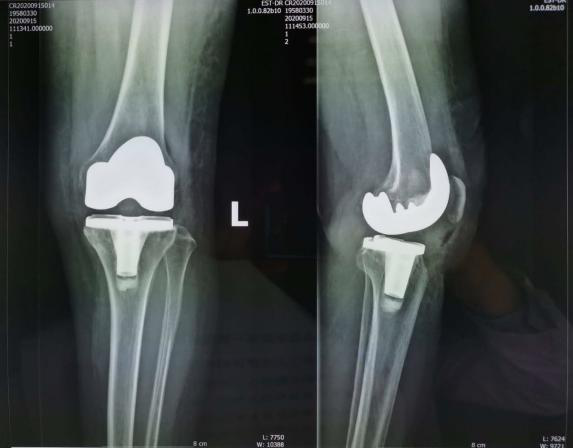

于阿姨手术前后对比图

通过前期的系统治疗效果没有明显改善后,包医一附院关节运动医学科副主任医师刘鹤鸣决定为于阿姨进行人工关节置换手术。“因为考虑到于阿姨的年龄比较大,怕一次做两条腿她耐受不了,所以暂时先为她做了一条腿的膝关节置换。”

目前,于阿姨已经康复出院,但她面临的,“是重新开始学走路。”

刘鹤鸣介绍,包医一附院关节运动医学科骨性关节炎的治疗会通过患者的轻重程度进行阶梯治疗,严格遵循中华医学会骨科学分会发布的《骨关节炎诊治指南》,通过止疼药、玻璃酸钠关节腔注射、关节镜清理、截骨术、人工关节置换等医疗手段为患者解除病痛的折磨。刘鹤鸣说,人工关节置换手术在国内已经发展了二、三十年,“但目前使用最多的进口假体和我们中国人有一些人种和解剖数据上的差异。为此,中华医学会骨科分会近几年做了大量的学术工作,通过收集西北和华北不同地区、人种的解剖学数据,设计了符合我们国人的国产假体,质量过关、好用,而且价格便宜,也更符合国人的解剖学数据。”